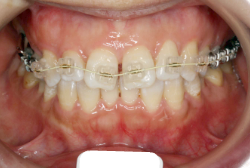

「ものがうまく噛めない」という主訴で来院したケースです。診断の結果、「骨格性反対咬合に伴う咬合不良+軽度叢生」と判明しました。原因としては特に下顎の左側が過成長したため、骨格性反対咬合になり、特に左側での噛み合わせが非常に悪くなっていると診断しました。初診時の写真を見ると、上下の正中線の大きなズレ、左側の噛み合わせの不良がはっきり分かります(黄色の矢印と緑の矢印は一致しているのが正しい状態です)。

そもそも、このような状態となっているのは骨の大きさに問題があるため生じていますので、場合によっては、「外科矯正」によって下顎の骨を外科的に縮めることで修正します。患者様が外科矯正をご希望されない場合は、従来ですと上下左右の小臼歯抜歯を行い矯正するのが普通です。

今回の患者様の場合は、「外科」も「小臼歯抜歯」も拒否されましたので、歯科矯正用アンカースクリュー(以下 アンカースクリュー)を用いて、下顎の歯列全体を後方に下げるという方法を取りました。

治療中の写真で、アンカースクリューより歯を後ろへ牽引しているのがお分かりいただけるかと思います。牽引を1年ほど続け、途中補助的に上下にゴムをかける(これを顎間ゴムと言います)手法なども追加し、全体で21ヶ月で治療を終えることが出来ました。

結局歯の本数を減らすことなく、すべてご自分の歯を残して、正しい配列と噛み合わせにすることができました。凸凹があまりひどくないため、簡単そうに見えると思いますが、このケースの初診の状態を見ると、熟練の矯正歯科医でも悩みのつきないケースです。まして、外科も出来ない、抜歯もイヤ、と言うことになると、従来の方法では治療不可能と考えられるのですが、アンカースクリューを使うことで最近は不可能が可能となってきました。